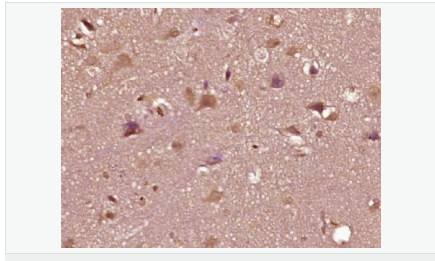

| 產(chǎn)品應(yīng)用 | WB=1:500-2000 ELISA=1:5000-10000 IHC-P=1:100-500 IHC-F=1:100-500 Flow-Cyt=1ug/Test IF=1:100-500 (石蠟切片需做抗原修復(fù)) not yet tested in other applications. optimal dilutions/concentrations should be determined by the end user. |

| 細(xì)胞定位 | 細(xì)胞核 細(xì)胞漿 |

| 產(chǎn)品介紹 | The androgen receptor gene is more than 90 kb long and codes for a protein that has 3 major functional domains: the N-terminal domain, DNA-binding domain, and androgen-binding domain. The protein functions as a steroid-hormone activated transcription factor. Upon binding the hormone ligand, the receptor dissociates from accessory proteins, translocates into the nucleus, dimerizes, and then stimulates transcription of androgen responsive genes. This gene contains 2 polymorphic trinucleotide repeat segments that encode polyglutamine and polyglycine tracts in the N-terminal transactivation domain of its protein. Expansion of the polyglutamine tract causes spinal bulbar muscular atrophy (Kennedy disease). Mutations in this gene are also associated with complete androgen insensitivity (CAIS). Two alternatively spliced variants encoding distinct isoforms have been described. [provided by RefSeq, Jul 2008] Function: Steroid hormone receptors are ligand-activated transcription factors that regulate eukaryotic gene expression and affect cellular proliferation and differentiation in target tissues. Transcription factor activity is modulated by bound coactivator and corepressor proteins. Transcription activation is down-regulated by NR0B2. Activated, but not phosphorylated, by HIPK3 and ZIPK/DAPK3. [ENZYME REGULATION] AIM-100 (4-amino-5,6-biaryl-furo[2,3-d]pyrimidine) suppresses TNK2-mediated phosphorylation at Tyr-267. Inhibits the binding of the Tyr-267 phosphorylated form to androgen-responsive enhancers (AREs) and its transcriptional activity. Subunit: Binds DNA as a homodimer. Part of a ternary complex containing AR, EFCAB6/DJBP and PARK7. Interacts with HIPK3 and NR0B2 in the presence of androgen. The ligand binding domain interacts with KAT7/HBO1 in the presence of dihydrotestosterone. Interacts with EFCAB6/DJBP, PELP1, PQBP1, RANBP9, RBAK, SPDEF, SRA1, TGFB1I1, ZNF318 and RREB1. Interacts with ZMIZ1/ZIMP10 and ZMIZ2/ZMIP7 which both enhance its transactivation activity. Interacts with SLC30A9 and RAD54L2/ARIP4. Interacts via the ligand-binding domain with LXXLL and FXXLF motifs from NCOA1, NCOA2, NCOA3, NCOA4 and MAGEA11. The AR N-terminal poly-Gln region binds Ran resulting in enhancement of AR-mediated transactivation. Ran-binding decreases as the poly-Gln length increases. Interacts with HIP1 (via coiled coil domain). Interacts (via ligand-binding domain) with TRIM68. Interacts with TNK2. Interacts with USP26. Interacts with RNF6. Interacts (regulated by RNF6 probably through polyubiquitination) with RNF14; regulates AR transcriptional activity. Interacts with PRMT2 and TRIM24. Interacts with GNB2L1/RACK1. Interacts with RANBP10; this interaction enhances dihydrotestosterone-induced AR transcriptional activity. Interacts with PRPF6 in a hormone-independent way; this interaction enhances dihydrotestosterone-induced AR transcriptional activity. Interacts with STK4/MST1. Interacts with ZIPK/DAPK3. Interacts with LPXN. Interacts with MAK. Part of a complex containing AR, MAK and NCOA3. Subcellular Location: Nucleus. Cytoplasm. Note=Predominantly cytoplasmic in unligated form but translocates to the nucleus upon ligand-binding. Can also translocate to the nucleus in unligated form in the presence of GNB2L1. Tissue Specificity: Isoform 2 is mainly expressed in heart and skeletal muscle. Post-translational modifications: Sumoylated on Lys-386 (major) and Lys-520. Ubiquitinated. Deubiquitinated by USP26. 'Lys-6' and 'Lys-27'-linked polyubiquitination by RNF6 modulates AR transcriptional activity and specificity. Phosphorylated in prostate cancer cells in response to several growth factors including EGF. Phosphorylation is induced by c-Src kinase (CSK). Tyr-534 is one of the major phosphorylation sites and an increase in phosphorylation and Src kinase activity is associated with prostate cancer progression. Phosphorylation by TNK2 enhances the DNA-binding and transcriptional activity and may be responsible for androgen-independent progression of prostate cancer. Phosphorylation at Ser-81 by CDK9 regulates AR promoter selectivity and cell growth. Phosphorylation by PAK6 leads to AR-mediated transcription inhibition. Palmitoylated by ZDHHC7 and ZDHHC21. Palmitoylation is required for plasma membrane targeting and for rapid intracellular signaling via ERK and AKT kinases and cAMP generation. DISEASE: Defects in AR are the cause of androgen insensitivity syndrome (AIS) [MIM:300068]; previously known as testicular feminization syndrome (TFM). AIS is an X-linked recessive form of pseudohermaphroditism due end-organ resistance to androgen. Affected males have female external genitalia, female breast development, blind vagina, absent uterus and female adnexa, and abdominal or inguinal testes, despite a normal 46,XY karyotype. Defects in AR are the cause of spinal and bulbar muscular atrophy X-linked type 1 (SMAX1) [MIM:313200]; also known as Kennedy disease. SMAX1 is an X-linked recessive form of spinal muscular atrophy. Spinal muscular atrophy refers to a group of neuromuscular disorders characterized by degeneration of the anterior horn cells of the spinal cord, leading to symmetrical muscle weakness and atrophy. SMAX1 occurs only in men. Age at onset is usually in the third to fifth decade of life, but earlier involvement has been reported. It is characterized by slowly progressive limb and bulbar muscle weakness with fasciculations, muscle atrophy, and gynecomastia. The disorder is clinically similar to classic forms of autosomal spinal muscular atrophy. Note=Caused by trinucleotide CAG repeat expansion. In SMAX1 patients the number of Gln ranges from 38 to 62. Longer expansions result in earlier onset and more severe clinical manifestations of the disease. Note=Defects in AR may play a role in metastatic prostate cancer. The mutated receptor stimulates prostate growth and metastases development despite of androgen ablation. This treatment can reduce primary and metastatic lesions probably by inducing apoptosis of tumor cells when they express the wild-type receptor. Defects in AR are the cause of androgen insensitivity syndrome partial (PAIS) [MIM:312300]; also known as Reifenstein syndrome. PAIS is characterized by hypospadias, hypogonadism, gynecomastia, genital ambiguity, normal XY karyotype, and a pedigree pattern consistent with X-linked recessive inheritance. Some patients present azoospermia or severe oligospermia without other clinical manifestations. Similarity: Belongs to the nuclear hormone receptor family. NR3 subfamily. Contains 1 nuclear receptor DNA-binding domain. SWISS: P10275 Gene ID: 367 Database links: Entrez Gene: 367 Human Entrez Gene: 11835 Mouse Omim: 313700 Human SwissProt: P10275 Human SwissProt: P19091 Mouse Unigene: 496240 Human Unigene: 39005 Mouse Unigene: 394224 Mouse Unigene: 439657 Mouse Unigene: 9813 Rat Important Note: This product as supplied is intended for research use only, not for use in human, therapeutic or diagnostic applications. AR是一個由917個氨基酸組成的蛋白質(zhì),位于雄激素靶組織細(xì)胞中或細(xì)胞表面上的特異分子部位或結(jié)構(gòu)。 AR在前列腺癌中起著重要的作用,研究表明AR的表達(dá)與組織分型形成一定的相關(guān)性 ,AR在高分化的腫瘤中表達(dá)較多,而在低分化的腫瘤中表達(dá)較少。用于前列腺癌的檢測,指導(dǎo)臨床治療,目前可用于乳腺癌、食道癌等各項腫瘤的研究。 |